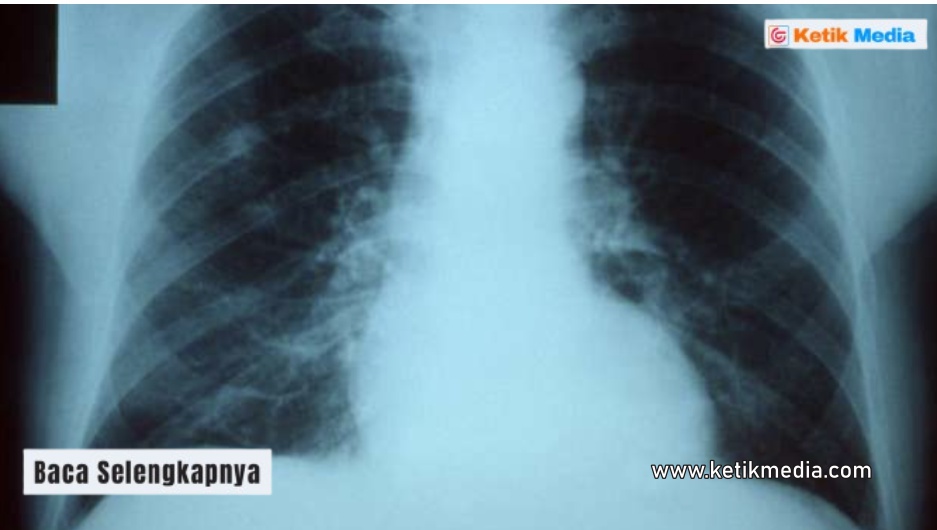

Hasil rontgen paru-paru basah menunjukkan gambaran bagian dalam tubuh yang sedang bermasalah. Tentu saja hasil rontgen paru paru bermasalah terlihat berbeda dengan hasil rontgen paru-paru normal.

Hasil rontgen paru-paru penderita pneumonia memiliki sejumlah tanda-tanda khusus. Termasuk bercak putih yang memenuhi bagian paru-paru.

Hasil rontgen paru-paru basah pada anak maupun orang dewasa kerap menunjukkan bercak dengan warnah putih. Temuan ini menggambarkan area paru-paru yang sedang mengalami peradangan akibat infeksi bakteri maupun virus.

Pneumonia yang terjadi karena adanya bakteri biasanya membentuk bercak dengan bentuk menyatu. Sementara pneumonia yang terjadi karena infeksi jamur memiliki bercak putih yang halus dan menyebar.

Contoh hasil rontgen paru-paru basah sering kali menunjukkan sudut diafragma dan dinding bagian bawah yang menjadi kabur. Pada kondisi normal, sudut kostofrenikus akan terlihat jelas dan tajam.

Kaburnya sudut ini bisa terjadi karena adanya cairan yang terdapat pada paru-paru. Pemeriksaan rontgen juga perlu dilanjutkan dengan pemeriksaan lainnya agar penanganan paru-paru basah menjadi lebih tepat.

Gambar paru-paru basah yang dilihat dari rontgen juga mempunyai perbedaan pada bagian mediastinum. Bagi yang belum tahu, mediastinum adalah sebuah struktur yang terletak pada bagian rongga dada. Bagian ini berisi pembuluh darah, organ jantung, dan juga trakea.

Dalam kondisi yang parah, cairan yang menyebabkan pneumonia bisa menekan organ-organ mediastinum ke arah yang berlawanan. Hal ini disebabkan penumpukan cairan dalam jumlah yang besar.

Tanda lain yang menunjukkan foto hasil rontgen paru-paru basah adalah garis diafragma yang menghilang. Pneumonia dapat menyebabkan hilangnya garis diafragma dalam kondisi yang cukup parah.

Kondisi ini terjadi karena paru-paru yang tidak lagi berisi udara. Pada penderita pneumonia, rongga paru-paru akan menjadi tempat berkembangnya bakteri. Baik yang berupa virus ataupun berupa jamur.

Hasil rontgen paru-paru basah seringkali memperlihatkan cairan di paru-paru yang melengkung ke arah atas. Pada saat itulah garis meniskus terlihat melengkung. Kondisi ini dapat terjadi pada tubuh pasien pneumonia.